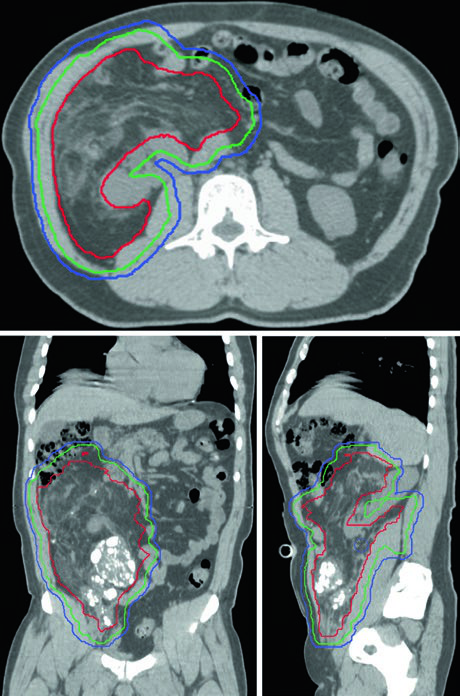

Los sarcomas retroperitoneales presentan retos completamente distintos a los de extremidades. Estos tumores crecen frecuentemente a volúmenes enormes, inicialmente desplazando y eventualmente invadiendo órganos adyacentes. La dosis recomendada es de 50 Gy en 25 fracciones a 50,4 Gy en 28 fracciones, administrada exclusivamente en el escenario preoperatorio.

Los márgenes radiales en el retroperitoneo son más conservadores (0,5–2,0 cm) mientras se mantienen 2 cm en dirección longitudinal, ya que la anatomía crítica adyacente impone límites estrictos. Cuando el tumor se aproxima a un hígado intacto, solo se incluyen 0,5 cm de parénquima hepático en el CTV. Posteriormente, se emplean márgenes de 2 cm para incluir tejido adiposo y vasos. El riñón ipsilateral puede sacrificarse si el contralateral demuestra función adecuada — en ese caso, la dosis al riñón no involucrado debe mantenerse tan baja como sea razonablemente posible.

| CTV | GTV + 2 cm longitudinal y 0,5–2,0 cm radial, limitado por barreras anatómicas y anatomía crítica. Si el tumor se aproxima a hígado intacto, 0,5 cm de hígado incluido. 2 cm de margen posterior para tejidos adiposos y vasos. Riñón ipsilateral puede sacrificarse si función contralateral es adecuada. |

| PTV | CTV + 0,5 cm según protocolo institucional. |

OAR: intestino delgado, hígado, médula espinal y pulmones. Simulación 4DCT recomendada. Dosis: 50 Gy/25 fx a 50,4 Gy/28 fx. Fuente: Target Volume Delineation and Field Setup, 2nd Edition (Table 32.3).

La simulación 4DCT se recomienda especialmente en el retroperitoneo, donde el movimiento respiratorio puede desplazar el tumor y los órganos adyacentes. Las calcificaciones intratumorales multifocales, cuando están presentes, sirven como excelentes sustitutos de fiduciales para la guía diaria de imagen en IMRT dirigida. El desplazamiento intestinal por el propio tumor es, paradójicamente, una ventaja del enfoque preoperatorio: con el tumor todavía in situ, las asas intestinales quedan naturalmente alejadas del campo de tratamiento.